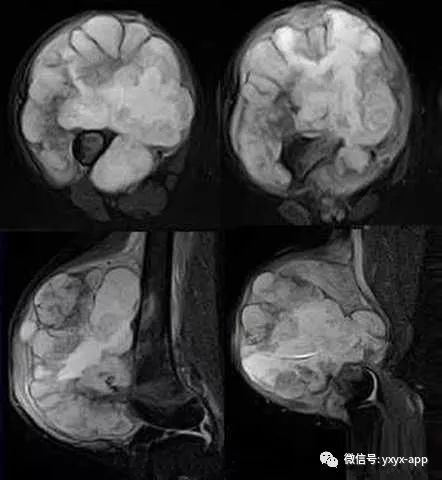

【基本资料】男,13岁

【主诉】右大腿上段肿胀三月

评论:青少年,股骨下段骨质致密度欠均匀,有溶骨性骨质破坏,边界模糊,有Codman三角形成,有与骨干垂直方向的放射形骨针,软组织肿胀。考虑骨肉瘤可能大。

术后病理:软骨肉瘤

1、中心型:多数为原发性,多发生于30岁以下,好发于长管状骨的干骺端,主要为骨质破坏、软组织肿块和肿瘤钙化,钙化量较大,尤以环状钙化为其特征,软组织肿块多较大,其内常有钙化。此型发展较快,预后较差。